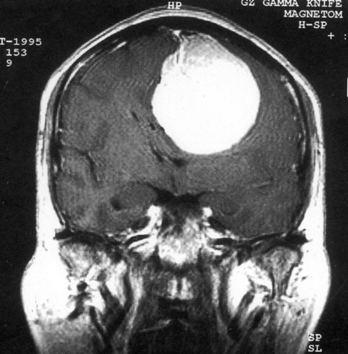

问题 病历摘要:??患者,男,40岁。发作性左下肢抽搐1年余,每次发作3~5分,每周发作1~2次。每次发作后感左下肢乏力,约半日后可自行恢复。既往身体健康。体检:神清,头顶部偏右有局限性骨性隆起(1.5×1.5cm),左鼻唇沟稍浅,伸舌居中。感觉、运动无明显异常。左浅反射减退,左下肢腱反射稍亢进,左Babinski征(-)。 术前的检查和治疗应包括下列哪些?提示:初步诊断考虑脑膜瘤,拟手术治疗。